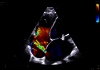

Conçue pour vous emmener plus loin, la nouvelle génération de cSound Pioneer se combine avec notre technologie de sonde avancée pour fournir des détails améliorés, un nouveau standard de flux couleurs et une incroyable imagerie 4D pour une confiance clinique dès le premier scan.